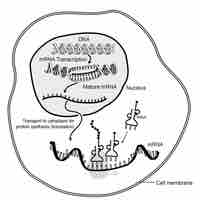

Protein synthesis inhibitors are substances that disrupt the processes that lead directly to the generation of new proteins in cells.

Antisense agents are short oligonucleotides that bind to target messenger RNA and inhibit protein synthesis.